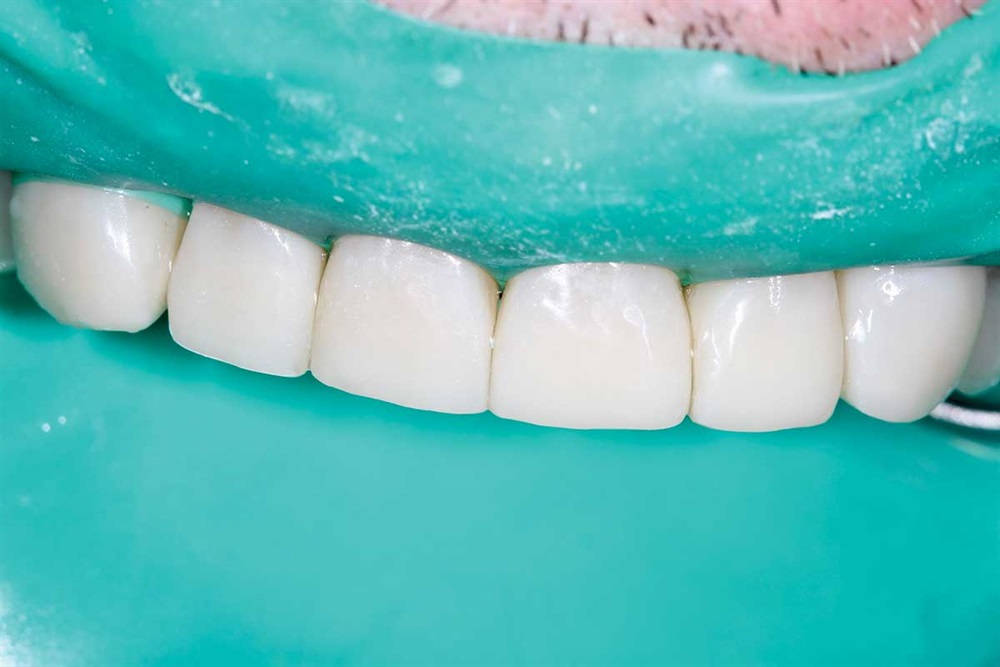

Fig. 43: Finished. If you have not tried Renamel, you really owe it to yourself and your patients to get a syringe and see how nice it looks. Dr. Buddy Mopper brought it to market well over 25 years ago.

Show Your Work

Figs. 44–46: The patient smiling. Never really could see his teeth when he smiled before.